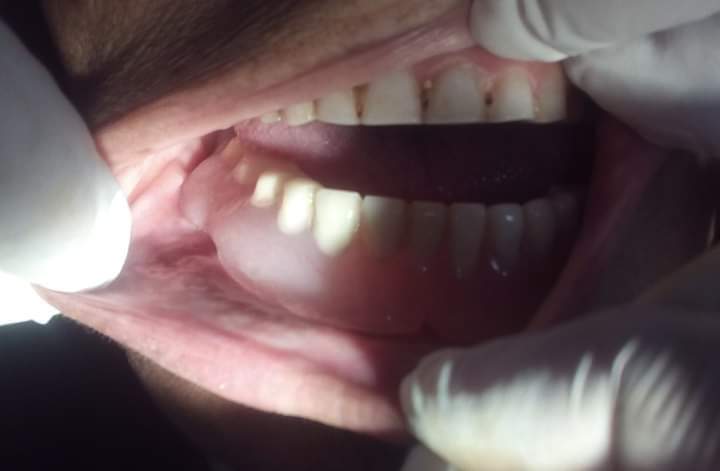

ثم تم استئصال الكيس بعد الإطمئنان لوجود كمية كافية من عظام الفك لمنع الكسر المحتمل وتم الإستعانة بعظم صناعي لملأ الفجوة وإعادة ضبط الطقم الأصلي ليكون داعما للجرح.

وبعد متابعة ستة أشهر كانت النتيجة المذهلة بتكون عظم جديد للفك واختفاء أثر الكيس وعودة حجم الفك إلى صورته الأصلية مع استخدام نفس طقم الأسنان الخاص بالمريضة في الطعام.